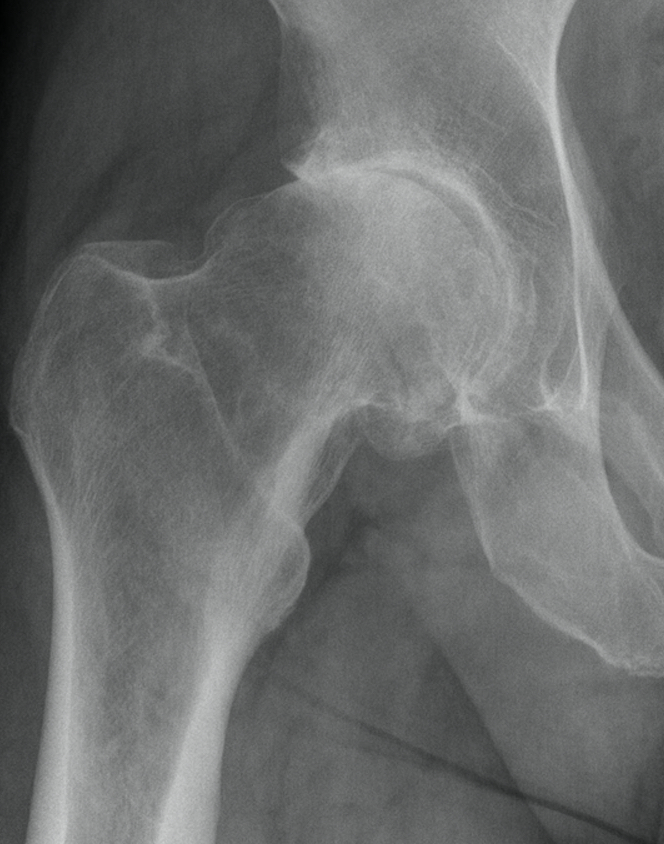

CLINICAL HISTORY: Right hip pain.

FINDINGS: AP and frog-leg lateral views of the right hip were obtained.

There is no fracture or dislocation. There is a severe degree of joint

space narrowing involving the superomedial aspect of the right hip with

associated dysplasia of the femoral head. Also noted is osteophyte

formation at the acetabulum. There is a mild degree of joint space

narrowing involving the superolateral aspect of the left hip joint. No

significant bone lesions are identified.

1. No evidence for acute osseous abnormality.2. Severe degenerative joint disease involving the right hip joint.

3. Mild degenerative joint disease involving the left hip joint.

I was sent to see a orthopedic surgeon who quickly cut (pun intended) to the chase. "Dave, if a normal hip for someone your age is a 1 and the world's worst hip is a 10, you are an 8, (note: after surgery he said it was more like a 9+ per the surgeon). You have only one option and that is a total hip replacement." He also told me that he has personally done over a 1,000 hips and he goes with proven technology.

The first thing he told me after surgery was "it was even worse than the x-rays indicated and it was filled with osteoarthritis."

Above is my arthritic right hip.